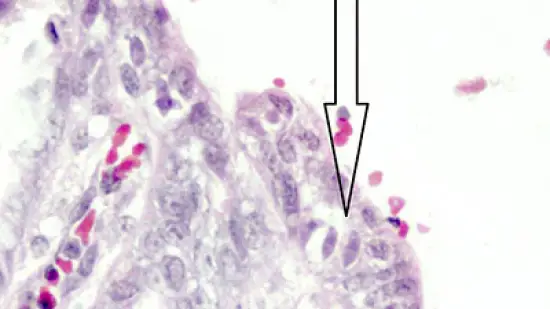

Quels sont les organismes (flèche) dans la muqueuse de l'intestin grêle de ce porcelet avec diarrhée?